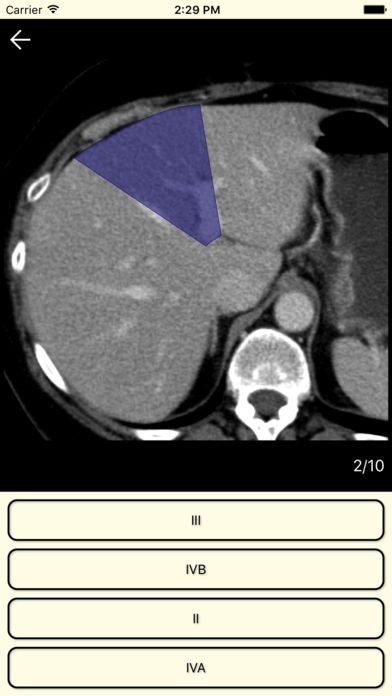

Browse an organ image slice by slice to learn it segmental structure. Zoom this image for a good view. Test yourself in the quiz.